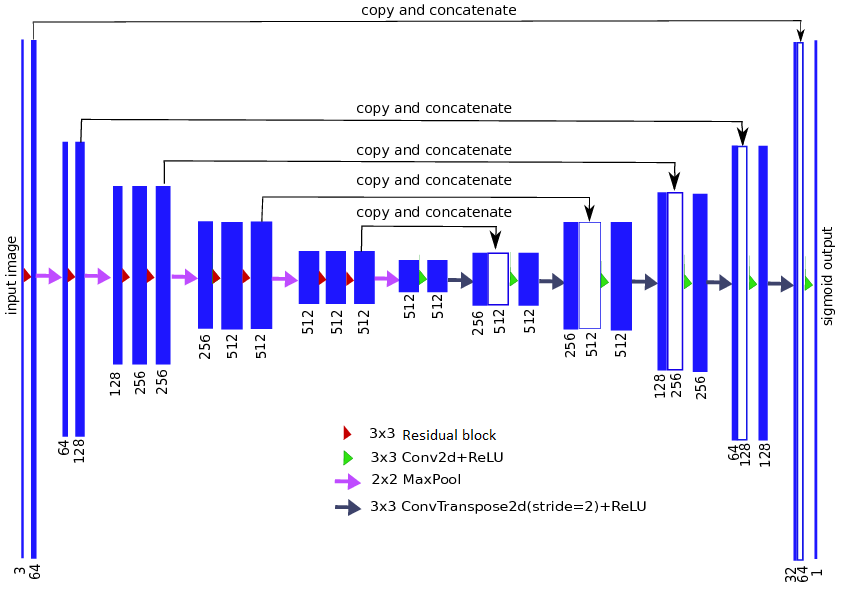

UNet简直是图像分割的神器,特别是在医疗图像分割的上,目前其各种变体网络仍是各种比赛的主力。Unet主要有2个特点:1.U型结构;2.skip connection.

– U型结构encoder的下采样和decoder的上采样的次数相同,这就保证了模型的输出恢复到原图片的分辨率,实现端到端的预测。

– skip connection的结构使模型结合不同level的feature map上进行学习,相比于FCN分割边缘更清晰。

同时Albunet的网络的encoder使用的是ResNet,其由何凯明大佬于2015年提出(Unet也是这一年提出,回过头看,这一年真的是丰收的一年),同样风靡至今。从理论上讲,越高级的特征,应该有越强的表征能力,而VGG网络证明,网络的深度对特征的表达能力至关重要。

理想情况下,当我们直接对网络进行简单的堆叠到特别长,网络内部的特征在其中某一层已经达到了最佳的情况,这时候剩下层应该不对改特征做任何改变,自动学成恒等映射的形式。也就是说,对一个特别深的深度网络而言,该网络的浅层形式的解空间应该是这个深度网络解空间的子集,但实际上,如果使用简单是网络堆叠,由于网络性能衰减,网络的效果反而越差。为了深度网络后面的层至少实现恒等映射的作用,作者提出了residual模块。

除了Albunet,作者还尝试了如下2种网络进行实验:

-

Resnet50: GitHub链接

-

SCSEUnet:也就是SENet((论文:squeeze-and-excitation network))